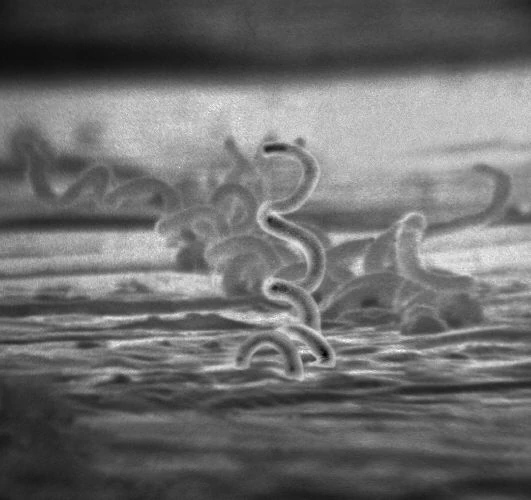

Treponema pallidum, the bacteria that causes syphilis, courtesty CDC, via Wikipedia